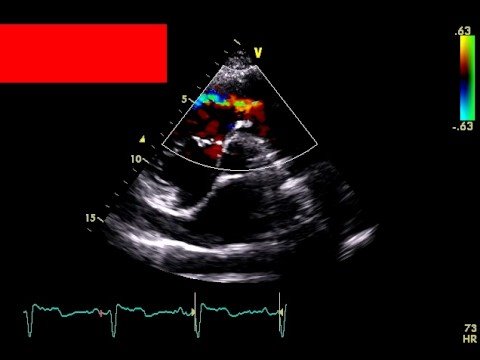

Predischarge Transthoracic Echocardiography after Surgery for Congenital Heart Disease: A Routine with a Reason?

Source: Predischarge Transthoracic Echocardiography after Surgery for Congenital Heart Disease: A Routine with a Reason? – Journal of the American Society of Echocardiography